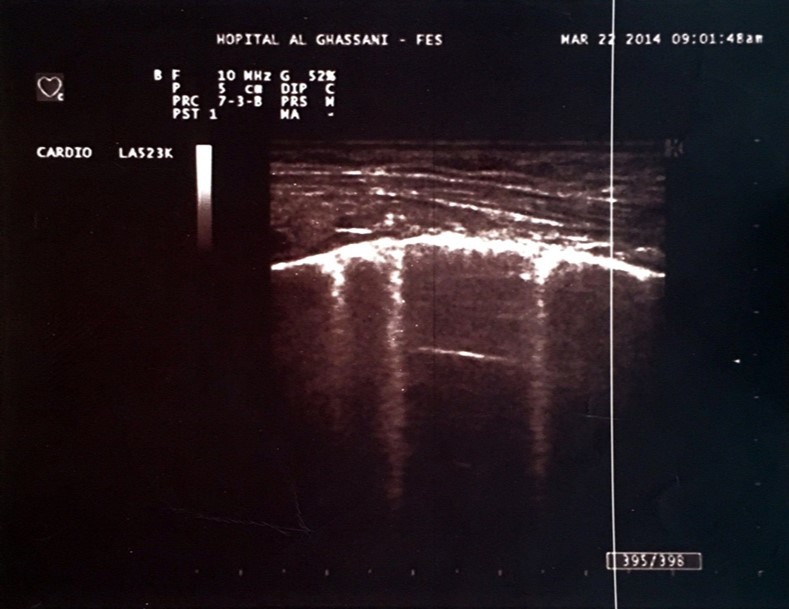

One of the most interesting tools is the use of the lung ultrasound to detect the presence of extravascular lung water (LW). In the presence of excessive LW, the US beam is reflected by subpleural thickened interlobular septa, a low impedance structure surrounded by air with a high acoustic mismatch. This US reflection generates hyperechoic reverberation artifacts between thickened septa and the overlying pleura that are known as “lung comets” or B-Lines 5. Lung comets are defined as vertical artifacts arising from the pleural line and extending to the edge of the screen that move synchronously with respiratory acts 6 (Figure 1).

Figure 1.Hyperechoic microreflections indicating the presence of extravascular lung water known as B-lines in one of our patients.